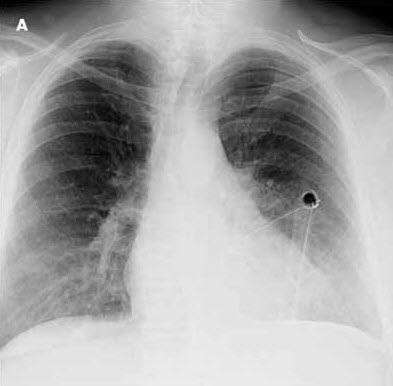

The posteroanterior chest radiograph suggests a rounded retrocardiac density in the left hemithorax (Figure 1). This is confirmed by the lateral view, which shows a large posterior lobulated shadow (Figure 2). The differential diagnosis at this point includes loculated pleural effusion, lung abscess without an air-fluid level, and thoracic empyema with or without an underlying malignancy. A chest CT scan delineates a 9 3 8-cm rounded density (Figure 3). The difference in homogeneity suggests a walled-off fluid collection with no evidence of air.

Intravenous levofloxacin and clindamycin are initiated in anticipation of percutaneous chest tube insertion into the lesion in the left hemithorax. The pleura in the left posterior lung base is slightly thickened; however, there is no evidence of an endobronchial obstructing lesion, hilar-mediastinal mass lesion, or pulmonary nodule. After the tube is placed, about 850 mL of foul-smelling brown fluid is evacuated by gravity (Figure 4). Microbiologic culture of the contents reveals Streptococcus intermedius, which is sensitive to levofloxacin. Cytologic analysis of the drainage material reveals no malignancy. Intravenous levofloxacin is continued for 10 days, followed by oral levofloxacin for another 2 weeks. Chest radiography and chest CT are repeated just before the chest tube is removed to assess whether surgery is needed. The CT scan shows almost complete resolution of the empyema.